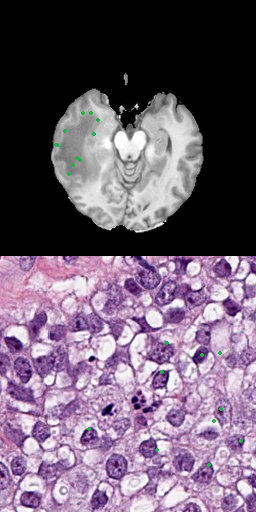

One approach is to use several positive points as input data that represent the goal label [8]. Using points as input is a precise method, allowing to preserve fine segmentation details but requires more annotation effort. When large areas are annotated, this is especially problematic. Figure 3 shows samples for using 3, 10, 50 or 100 points for the radiology and pathology data.

Refer to caption

(a) 3 positive points

(b) 10 positive points

(c) 50 positive points

(d) 100 positive points

Figure 3: Results for different number of positive points without bounding box